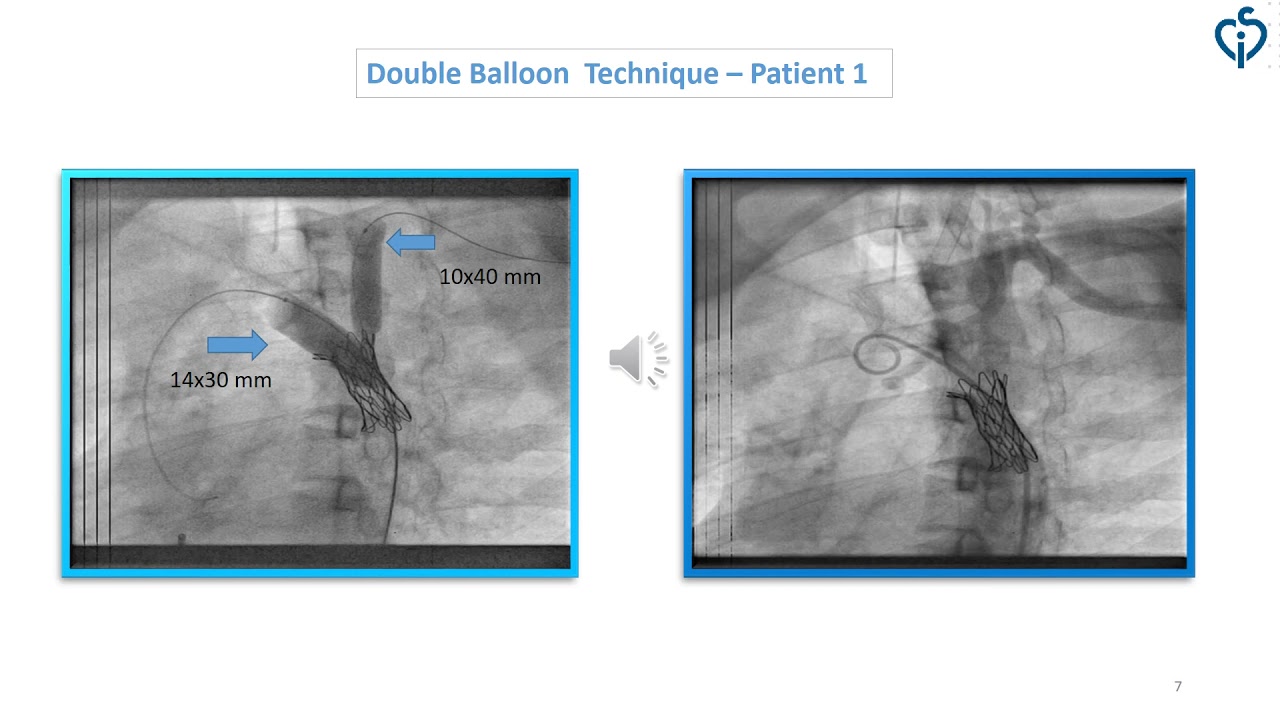

Double Balloon Technique for Stent Implant in Patients with Severe Coarctation of Aorta (CoA)

By: Ahsan Beg, CPE Institute of Cardiology Multan, Multan, Pakistan